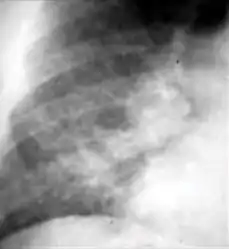

Chest x-ray showing coarse reticulonodular densities on the lower right lung of post-primary pulmonary TB.

3. Nodule with poorly defined margins - Round density within the lung parenchyma, also called a tuberculoma. Nodules included in this category are those with margins that are indistinct or poorly defined (tree-in-bud sign[3]). The surrounding haziness can be either subtle or readily apparent and suggests coexisting airspace consolidation.

Chest x-ray showing nodule with margins that are indistinct or poorly defined (tree-in-bud sign) in post-primary pulmonary TB.